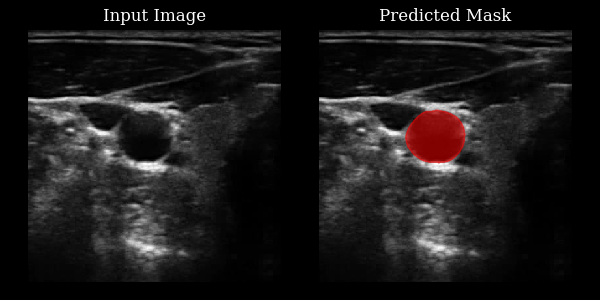

This section demonstrates how to use the CarotidSegmenter model from the zea library to segment the carotid artery in ultrasound images. The model predicts a mask highlighting the carotid region for a given input image.

Carotid Example Output